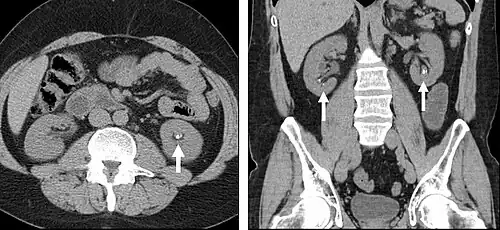

FIGURE 3. Axial (left) and coronal (right) CT angiography images of the abdominal aorta evaluating for aortic aneurysm.

CT angiography (CTA) is highly effective for evaluation of the arterial system, and has largely replaced conventional angiography due to the lower risk profile and ability to survey the entire abdomen. Images are acquired after a rapid bolus of intravenous contrast material (3-7 cc/s) during the arterial phase (15–35 seconds after injection) when the concentration of contrast material in the arterial system is high (figures 3). Images are usually acquired using narrow collimation (<1 mm) and can be retrospectively reconstructed using dedicated 3-dimensional workstations and software. CTA is commonly used in the head and chest in the evaluation of pulmonary emboli, aneurysms, vascular malformations, dissection, bleeding and ischemia. Indications for early arterial phase imaging include: evaluation of aneurysms or dissections (cerebral, aortic, etc.), hepatic, splanchnic or renal arterial anatomy, and arterial imaging in liver or kidney transplantation. Single phase arterial imaging is often used in the evaluation of trauma patients either a complete chest/abdomen/pelvis examination with arterial phase imaging of the chest and portal venous phase imaging of the abdomen/pelvis or just a portal venous phase of abdomen and pelvis depending on the mechanism and severity of the trauma. CTA is also commonly performed in the abdomen and pelvis for evaluating vascular malformations and in the evaluation of bleeding. Mesenteric ischemia can also be evaluated using CT angiography. CTA of the abdomen and pelvis is often performed in combination with a CTA for evaluating the extremity vasculature.